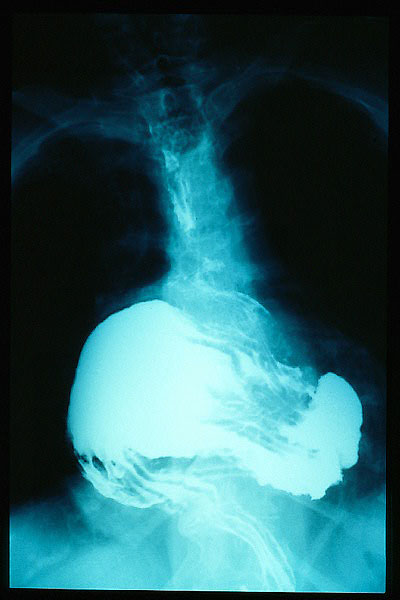

Hernia de hiato gigante.

Hernia de hiato por deslizamiento al TGED.

Hernia de hiato por deslizamiento al TEGD.